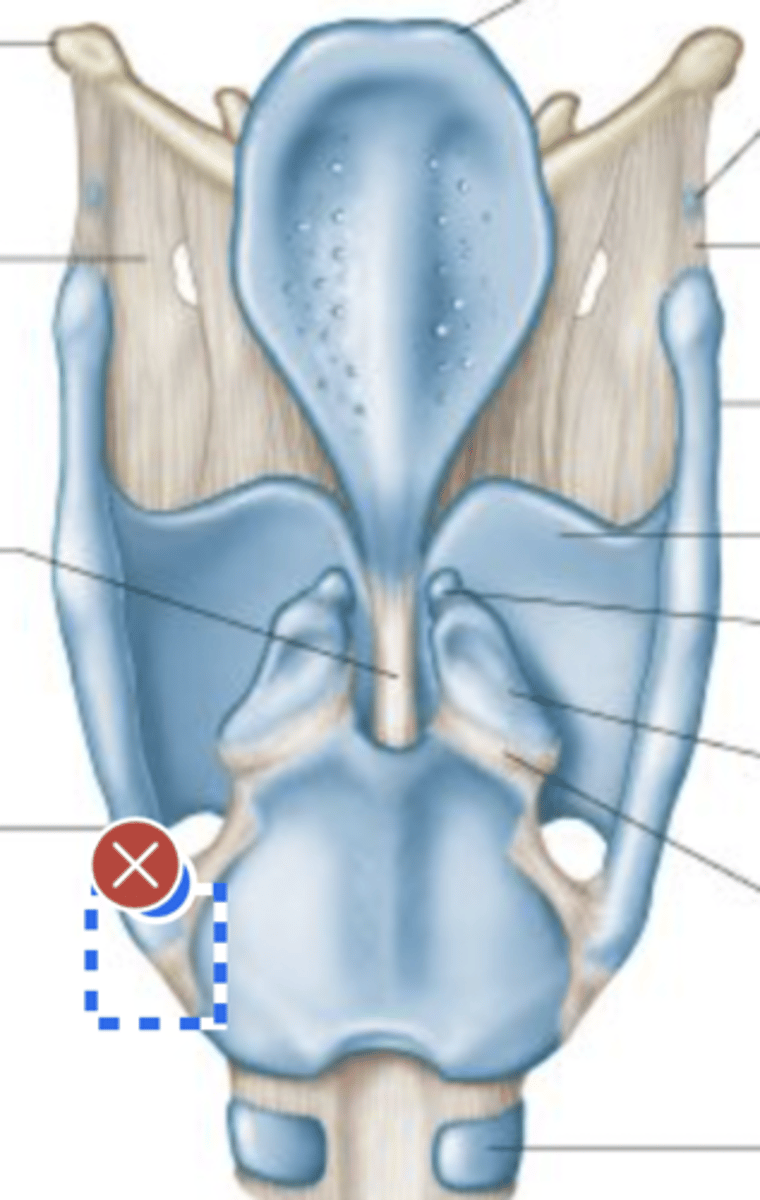

Label hyoid bone (anterior view)

Label epiglottis (anterior view)

Label Thyroid cartilage (anterior view)

Label cricoid cartilage (anterior view)

Label 2nd tracheal ring (anterior view)

Label left cricothyroid joint (anterior view)

Label Cricoid cartilage (posterior view)

Label Right arytenoid (posterior view)

Label Left cricothyroid joint (posterior view)

Label Laryngeal surface of epiglottis (posterior view)

Label 1st tracheal ring (posterior view)